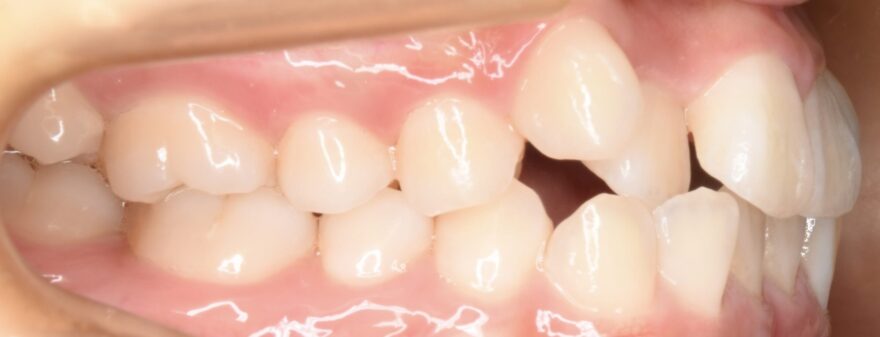

初診時の口腔内写真

上の八重歯が気になります。

八重歯の内側への移動量がとても多いことがわかります。